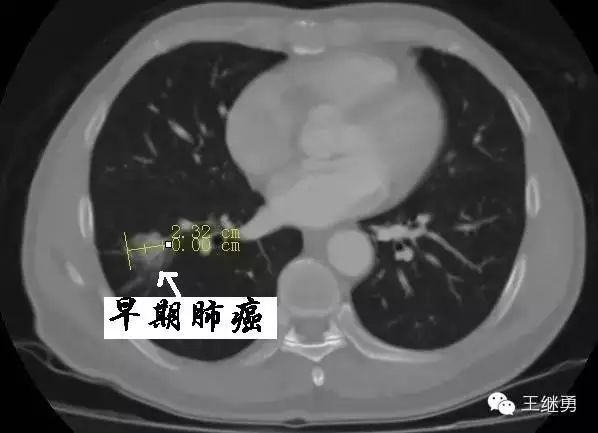

胸部ct看着像肺炎,最终确诊为肺癌!这种特殊肺癌易被误诊成肺炎

肺癌ct

肺癌ct图片